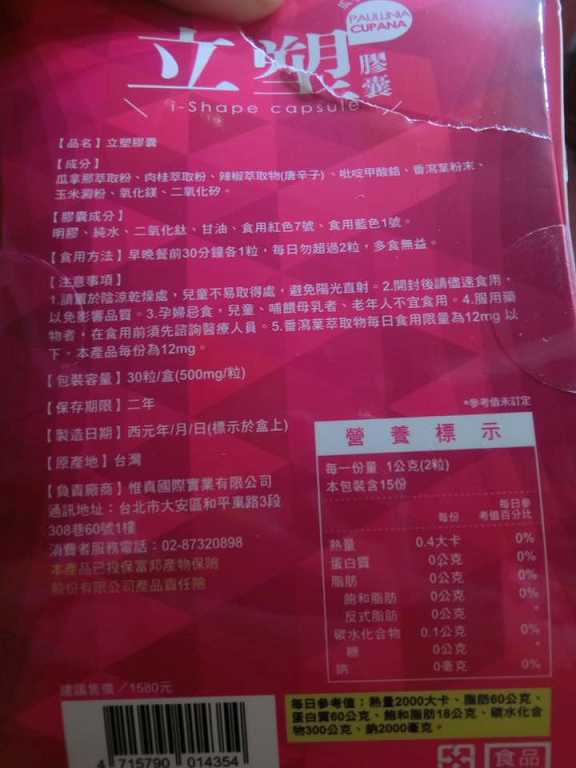

Supercut塑魔纖立塑膠囊的成分有:瓜拿那萃取粉、肉桂萃取粉、辣椒萃取物(唐辛子)、吡啶甲酸鉻、番瀉葉粉末、玉米澱粉、氧化鎂、二氧化矽。

之前上過相關課程,成分表是依照每項成分的多寡來排列順序,排在最前面的就是產品的主要成分!

那我就跟大家分享瓜拿那萃取粉、肉桂萃取粉和辣椒萃取物吧

瓜拿那萃取和辣椒萃取是可以幫助纖體瘦身常見的營養素!

1.「瓜拿那」是原產於亞馬遜流域的一種藤蔓植物,富含酵素可以幫助排便順暢,並且能抑制脂肪分解酵素,此外也有降低食慾的效果喔~~萃取物中含有天然咖啡因,可以提高新陳代謝率以及排出多餘水分!

2.「辣椒萃取物」則是可以幫助體內脂肪燃燒、增加卡路里的消耗,達到防止脂肪積聚的效果

3.「肉桂萃取物」看到肉桂,就想到麥當勞的蘋果派或是手掌麵包,雖然很多人很害怕那味道,但艾哥愛死肉桂了!!!!肉桂在古代被視為是最有價值的東方香料之ㄧ,中世紀時,肉桂的聲望僅次於昂貴的黑胡椒,除了香料和薰香價值, 傳統上肉也被用來治療消化不良、脹氣、關節疼痛、出血和經痛,研究也指出肉桂可以促進新陳代謝喔

食用方式:早晚餐前30分鐘各1粒,每日不超過2粒。(多食無益)

番瀉葉萃取物每日食用限量為12mg以下,

番瀉葉萃取物每日食用限量為12mg以下,